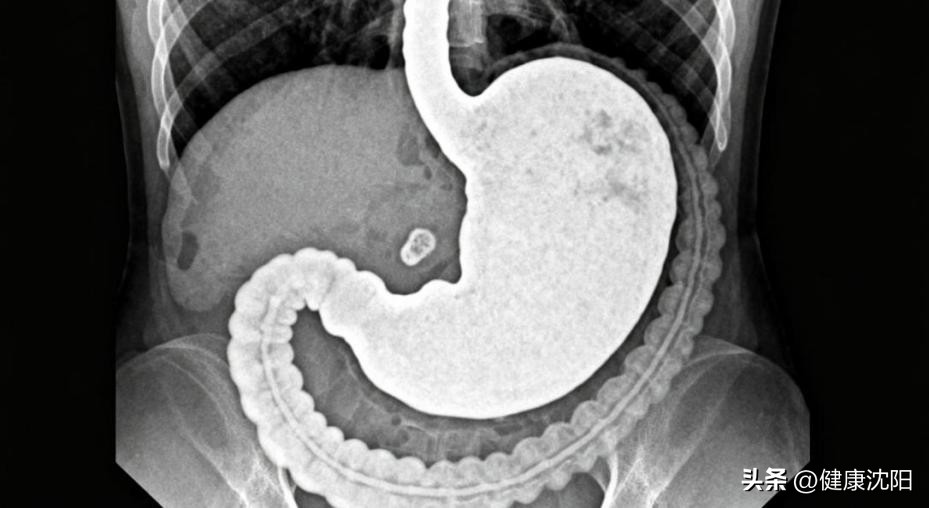

受检者口服医用钡剂(一种不被人体吸收的白色粉末混悬液),钡剂会附着在胃肠道黏膜表面,再通过X线透视或拍片,清晰呈现胃肠道的形态、轮廓和蠕动情况,从而帮助医生初步排查胃溃疡、食管癌、胃癌、十二指肠溃疡等病变。